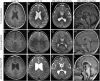

Figure 2. Representative MRI of pachygyric frontal cortex in FOXG1 patients

Representative images at the level of centrum semiovale in axial T1-weighted (A, E, I) and T2-weighted (B, F, J) MRI, at the level of lateral ventricles (third column) and midline sagittal (right column). Each row shows images from the same patient respectively: (A–D) Str02 aged 19 months; (E–H) Ang01 aged 23 months; (I–L) Rou01, aged 34 months. The cortex appears mildly thick with a clear predominance in the frontal lobes. The appearance of pachygyria is accentuated by the underdevelopment of frontal lobes. T2-weighted (C, G, K) MRI at the level of the internal capsule showing associated myelination delay, with mature myelin only visible in both internal capsules (G and K). T1-weighted midline sagittal sections showing the wide range of appearance of the corpus callosum, from hypoplastic and thin (D, L) to thick with underdevelopment of the genu (H).